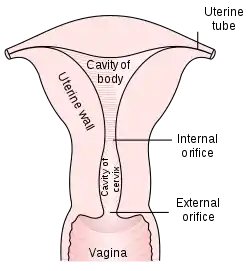

Structure

The uterus is located within the pelvic region immediately behind and almost overlying the bladder, and in front of the sigmoid colon. The human uterus is pear-shaped and about 7.6 cm (3.0 in) long, 4.5 cm (1.8 in) broad (side to side), and 3.0 cm (1.2 in) thick.[1][2] A typical adult uterus weighs about 60 grams. The uterus can be divided anatomically into four regions: the fundus – the uppermost rounded portion of the uterus, the corpus (body), the cervix, and the cervical canal. The cervix protrudes into the vagina. The uterus is held in position within the pelvis by ligaments, which are part of the endopelvic fascia. These ligaments include the pubocervical ligaments, the cardinal ligaments, and the uterosacral ligaments. It is covered by a sheet-like fold of peritoneum, the broad ligament.[3]

From outside to inside, regions of the uterus include:

- Cervix uteri – "neck of uterus"

- External orifice of the uterus

- Cervical canal

- Internal orifice of the uterus

- Body (Latin: Corpus)

- Uterine cavity

- Fundus

The uterus has three layers, which together form the uterine wall. From innermost to outermost, these layers are the endometrium, myometrium, and perimetrium.[5]